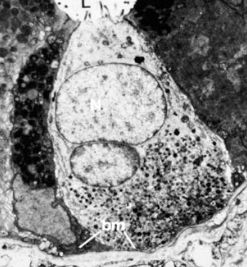

What cell layer varies most in the GI tract?

Epithelium